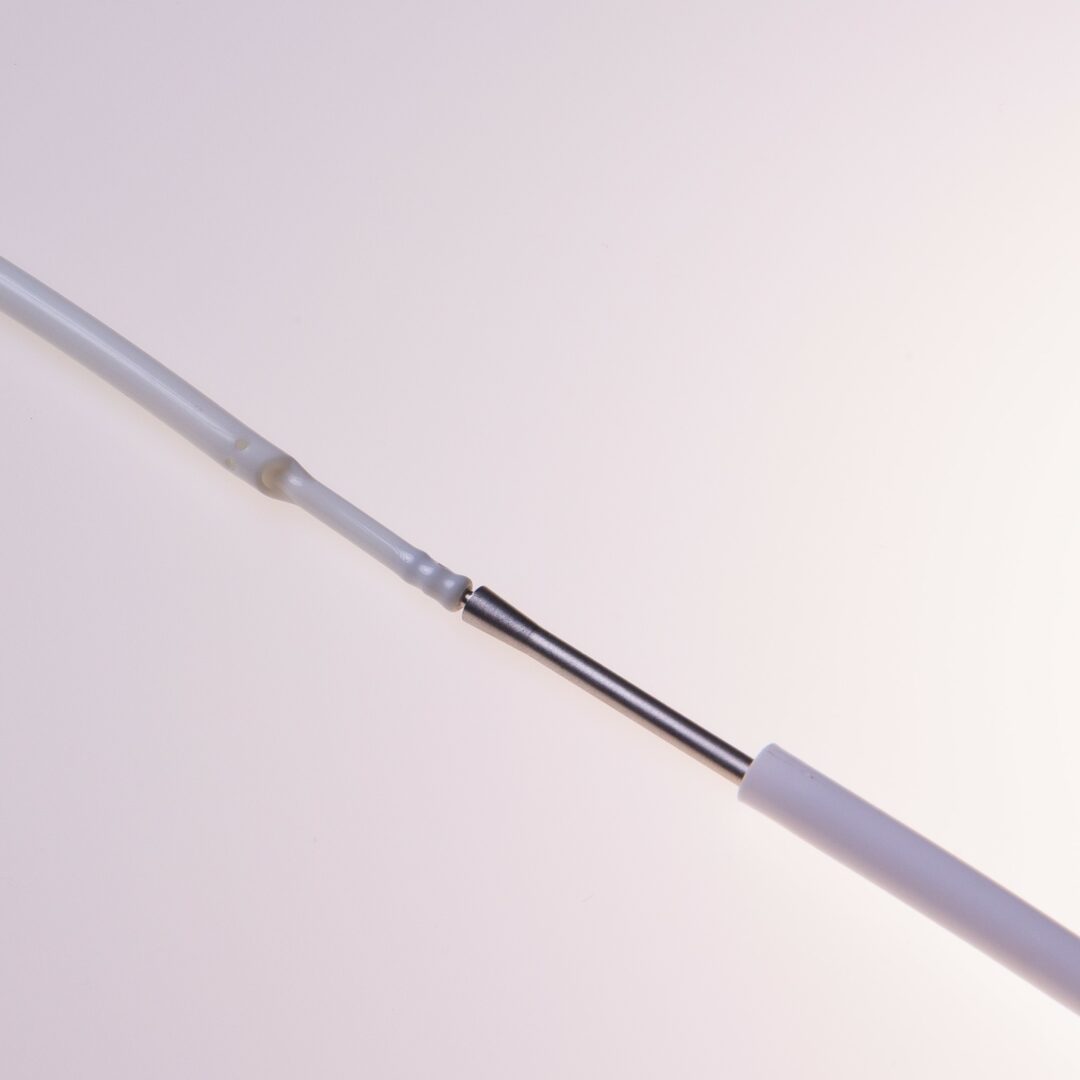

Tip Design

Der HFS Hemo Flow® verfügt über ein „Tap Tip“ Spitzendesign.